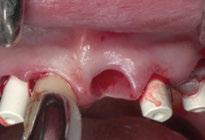

Para ilustrar el proceso, presentamos el caso de una mujer joven diagnosticada de carcinoma adenoide quístico en la región posterior del hemipaladar izquierdo (Figuras 1 y 2). El procedimiento quirúrgico realizado fue una

maxilectomía parcial que incluyó las piezas 24-26 y desde el reborde alveolar hasta la base del cráneo (Figuras 3 y 4). En este caso, la órbita y el globo ocular pudieron ser preservados. La reconstrucción inmediata se realizó mediante un colgajo de músculo temporal homolateral (Figura 5) y el defecto de la fosa temporal fue cubierto mediante una malla de titanio. Posteriormente, la paciente recibió radioterapia (Figuras 6 y 7). 2 años más tarde se diseñó un IS con anclaje en el arbotante nasomaxilar, zona subnasal izquierda

y lo que se pudo preservar del hueso malar. Se añadió una malla sinterizada infraorbitaria para dar volumen a la mejilla y se planificaron dos brazos de conexión que emergieran en las posiciones 24 y 26 de forma subgingival (Figuras 8 y 9). La superficie interna que apoyaba en el hueso era de titanio microrrugoso, y la superficie externa y conectores de titanio pulido y hexágono externo universal (Figuras 10 y 11). La cirugía se hizo bajo anestesia general en infiltración con anestesia local (4% articaína, 1:100.00 epinefrina), levantando el

colgajo cutáneo de la mejilla por vía intraoral, preservando el colgajo temporal para no comunicar con el remanente de la cavidad naso maxilar (Figura 12). Se emplearon 10 tornillos de osteosíntesis de 1,9 mm y la estabilidad primaria obtenida fue excelente (Figura 13)

4 meses después de la cirugía la encía estaba completamente cicatrizada y las conexiones de los implantes tipo hexágono externo universal quedaron a nivel yuxtamucoso. En este caso no se requirió el empleo de pilares transepiteliales y las impresiones fueron tomadas